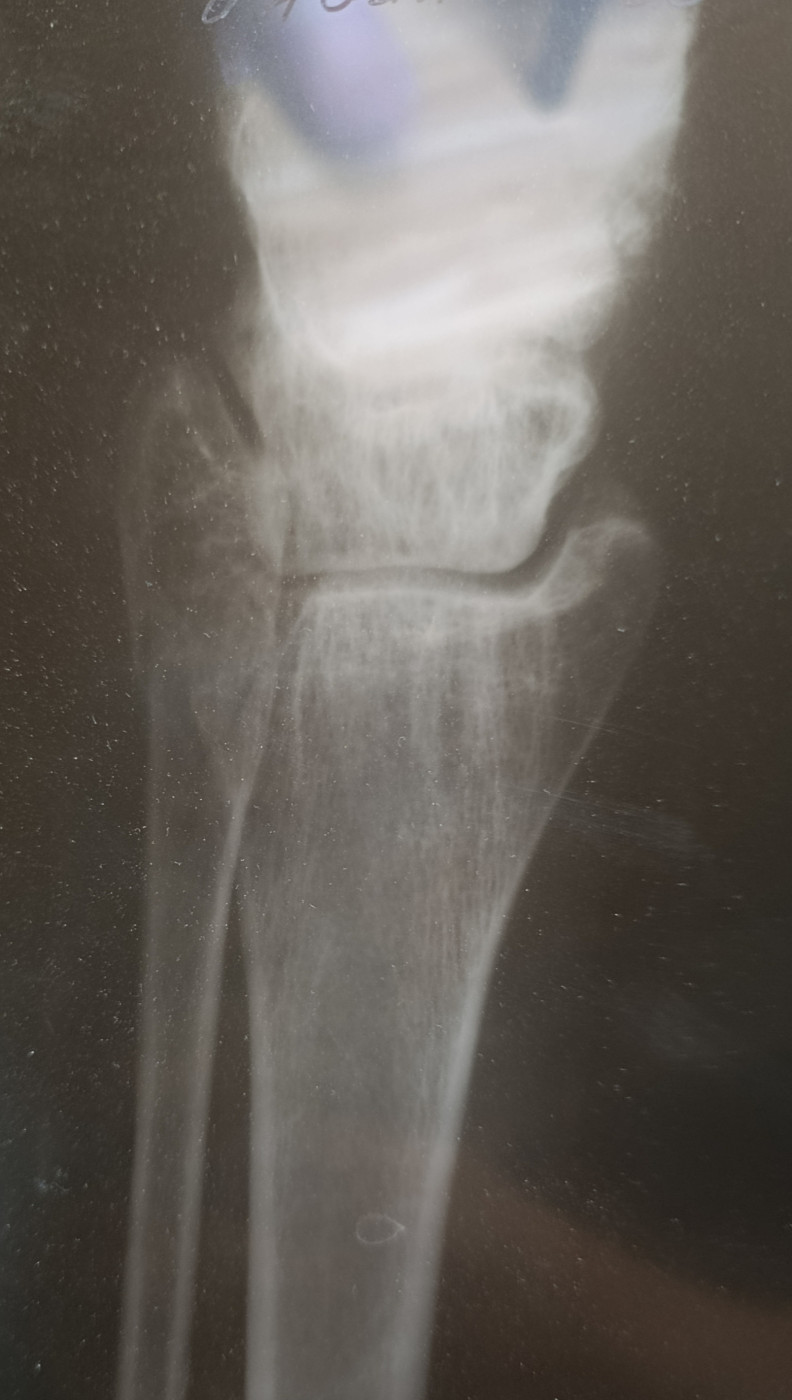

Вывих правой стопы снаружи и сзади, перелом обеих лодыжек и заднего края большеберцовой кости правой голени

Пластика ПКС